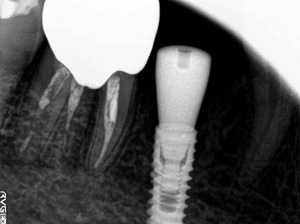

@@R.S‚³‚ñ@56Î —«  ‘åŠw‹³Žö @Žèp“ú@‚Q‚O‚O‚W”N ‚QŒŽ ‚X“úi“yj@㉺Š{  ƒm[ƒxƒ‹ƒKƒCƒhŽg—p@Ö¬“à’ÁÖ@•¹—p@@@

@@@@@ãŠ{  All on ‚U@‘¦Žž‰Ád@@

@@@@@@@@@@@@@ Rpl Tapered Rp  ‚P‚O mm(‚U–{)

@@@@@‰ºŠ{¶‰E@‘¦Žž‰Ád@ ‚R Unit Bridge@

@@@@@@@@@@@ @Rpl Tapered Rp  ‚P‚O mm(‚S–{)@@–ƒWƒ‹ƒRƒjƒAƒNƒ‰ƒEƒ“‚ÅÅI•â’Ô